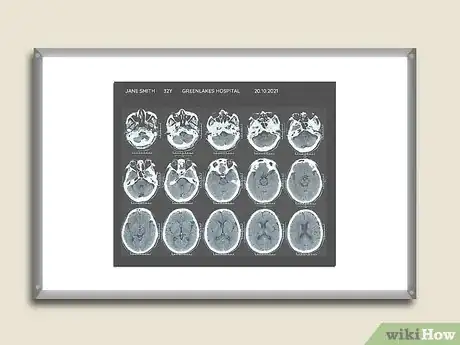

A computed tomography (CT) scan can create cross-sectional images of any part of your body using special X-rays and a computer.[1] This type of radiology study is an important part of diagnosing medical diseases like strokes, cancers, and infections in the abdomen like appendicitis. You can learn to read a CT scan if you understand the normal anatomy and what the shades of white, grey, and black on the films mean.

1Take note of the shades of white, gray, and black. The soft tissues, fat, air, and bone inside of you are represented in these different shades. An unexpected color in a part of your body could be a sign of an abnormality.

- Dense tissues like bone show up as white areas. Both air and fat show up as dark gray or black. Your soft tissues and any fluid, including blood, will show up in various shades of gray. Different types of contrast, which shine bright white on the films, are used to better define the structures inside you. You swallow one type to show the fluid inside your stomach and intestines. But, another type is injected into your into a vein to show the blood in your vessels or the fluid around an organ. The latter could be a sign of inflammation, infection, or bleeding.

- A specific example is looking at the shading on the CT of your brain and knowing you have had a stroke. The bone of your skull is normal and shines bright white like an egg shell around the grays and black of your brain tissue. But, there is a small, faint white area surrounded by the grays and black where the stroke has occurred. Your brain tissue was deprived of blood flow in this area. The fluid which leaked out of your injured brain cells has contrast in it. This fluid is white, but it is not as bright as your skull.

1Read the information on the CT scan. Check to see what is printed on the films to determine they are yours and what part of the body is represented in the films.

- You should see your name and other identifying information like your birthdate. The name of the hospital or medical facility where the films were taken and the date the study was performed should be printed on each film. You do not want to look at someone else’s films and become upset if you see an abnormality.

- Your expectations about what you will see are determined by what part of your body was studied. The CT of your brain will be compact with your brain encased inside the thin bone of your skull. The CT of your leg or arm will be compact but it will have length; the scan will have images of your bones and the surrounding soft tissue (muscle and fat). The CT of your abdomen will be large and very complex because you will be seeing things like your small intestines curled up like a snake right next to your kidneys, liver, spleen, etc.